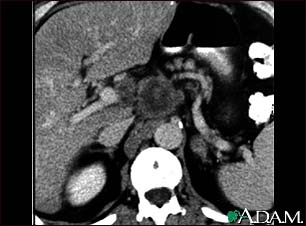

Pancreatic cancer, CT scan

A CT scan of the upper abdomen showing a tumor (pancreas carcinoma) in the head of the pancreas, seen here in the middle of the picture.